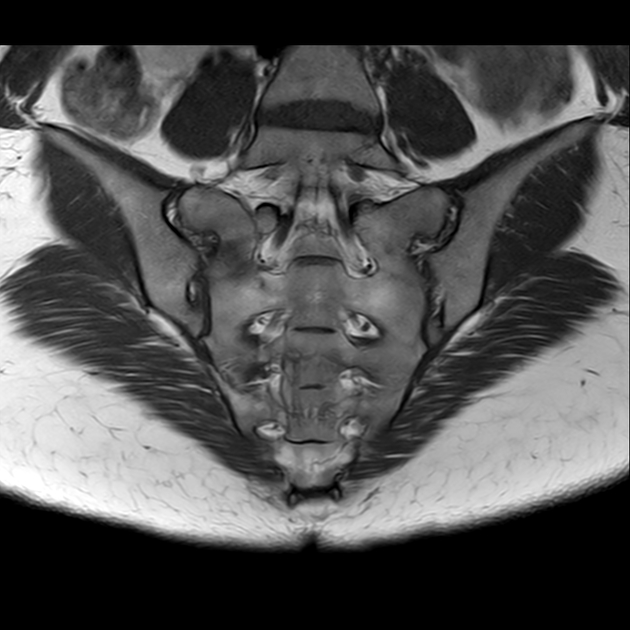

磁共振检查:

T1

2、单侧或双侧骶骨翼骨皮质断裂,见迂曲纵行骨折线,大致与骶髂关节平行(双侧多见);

3、骶骨体部看见骨折线

4、冠状位上述骨折形成 “H”型 ,故有人称东风本田征(为了方便记忆)

6、磁共振上可以发现骨折线周边明显的骨髓水肿,增强扫描明显强化

磁共振影像表现